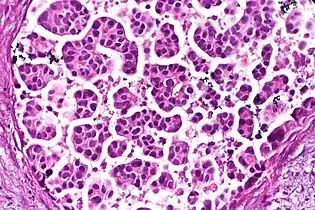

- Architectural pattern of any suspicious cells, in this case nests of cells, as well as components of the intervening stroma.

Major histopathologic architectural patterns include:

- Nests: islands of cells of similar type.

- Cribriform: Solid with multiple clear spaces.